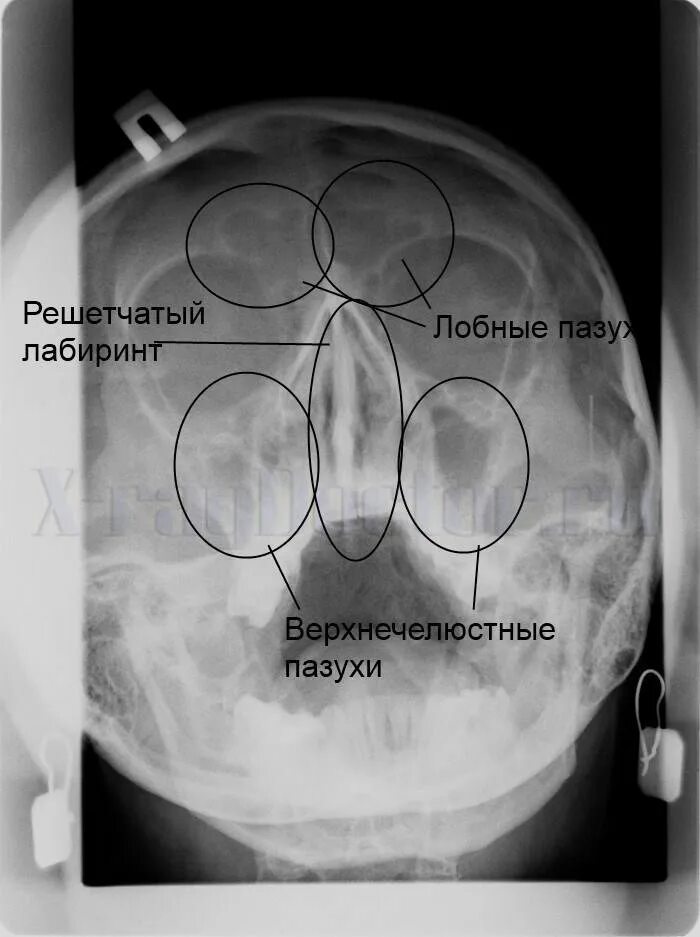

Утолщение верхнечелюстной пазухи что это значит